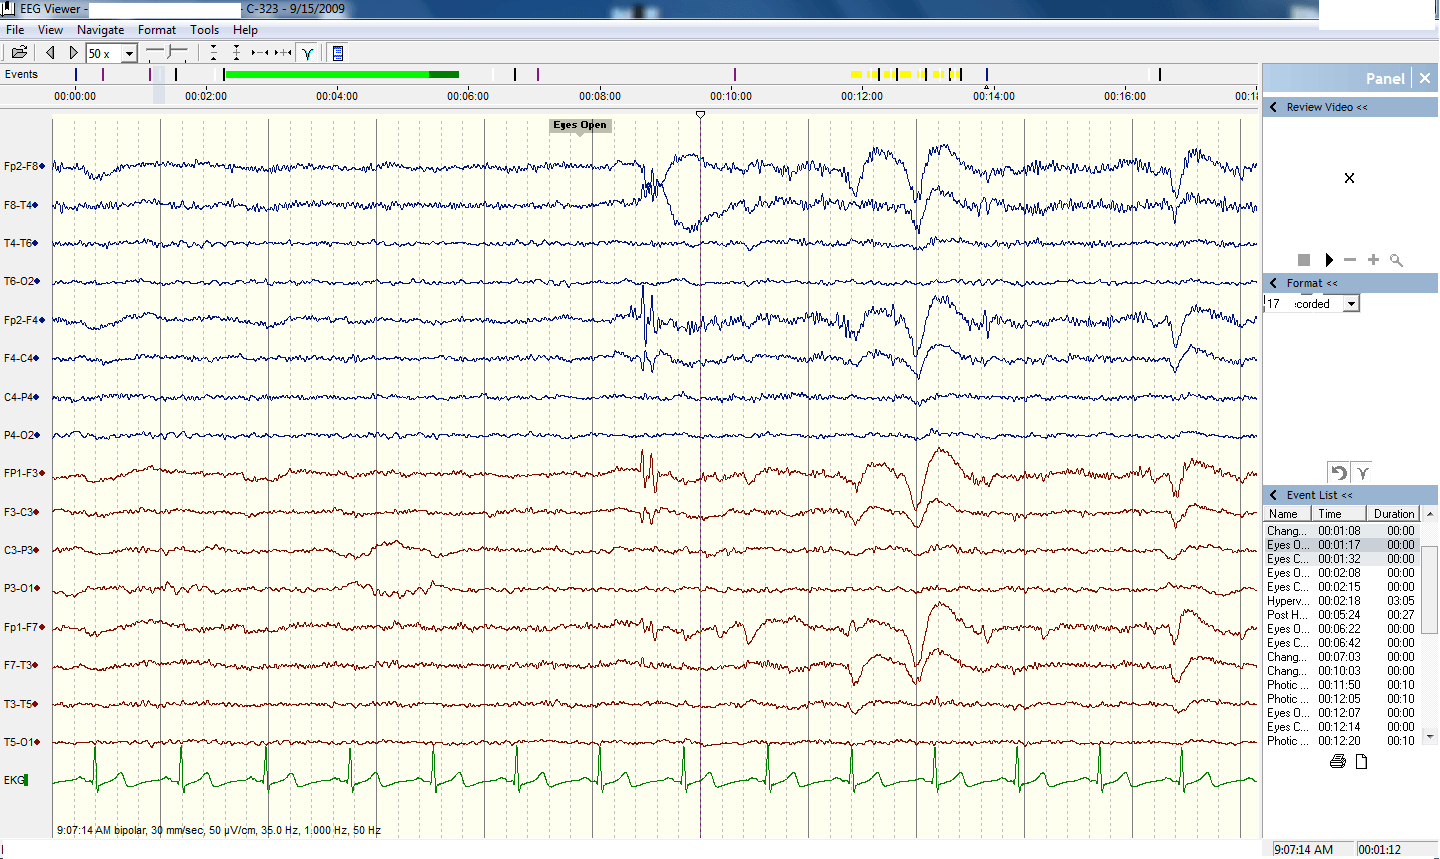

Так выглядит ЭЭГ. В ECoG электроды подключаются непосредственно к мозгу, но мы вам это показывать не будем

Примерно так выглядят показания снятые с ECoG, которые затем преобразуются в цифровой код